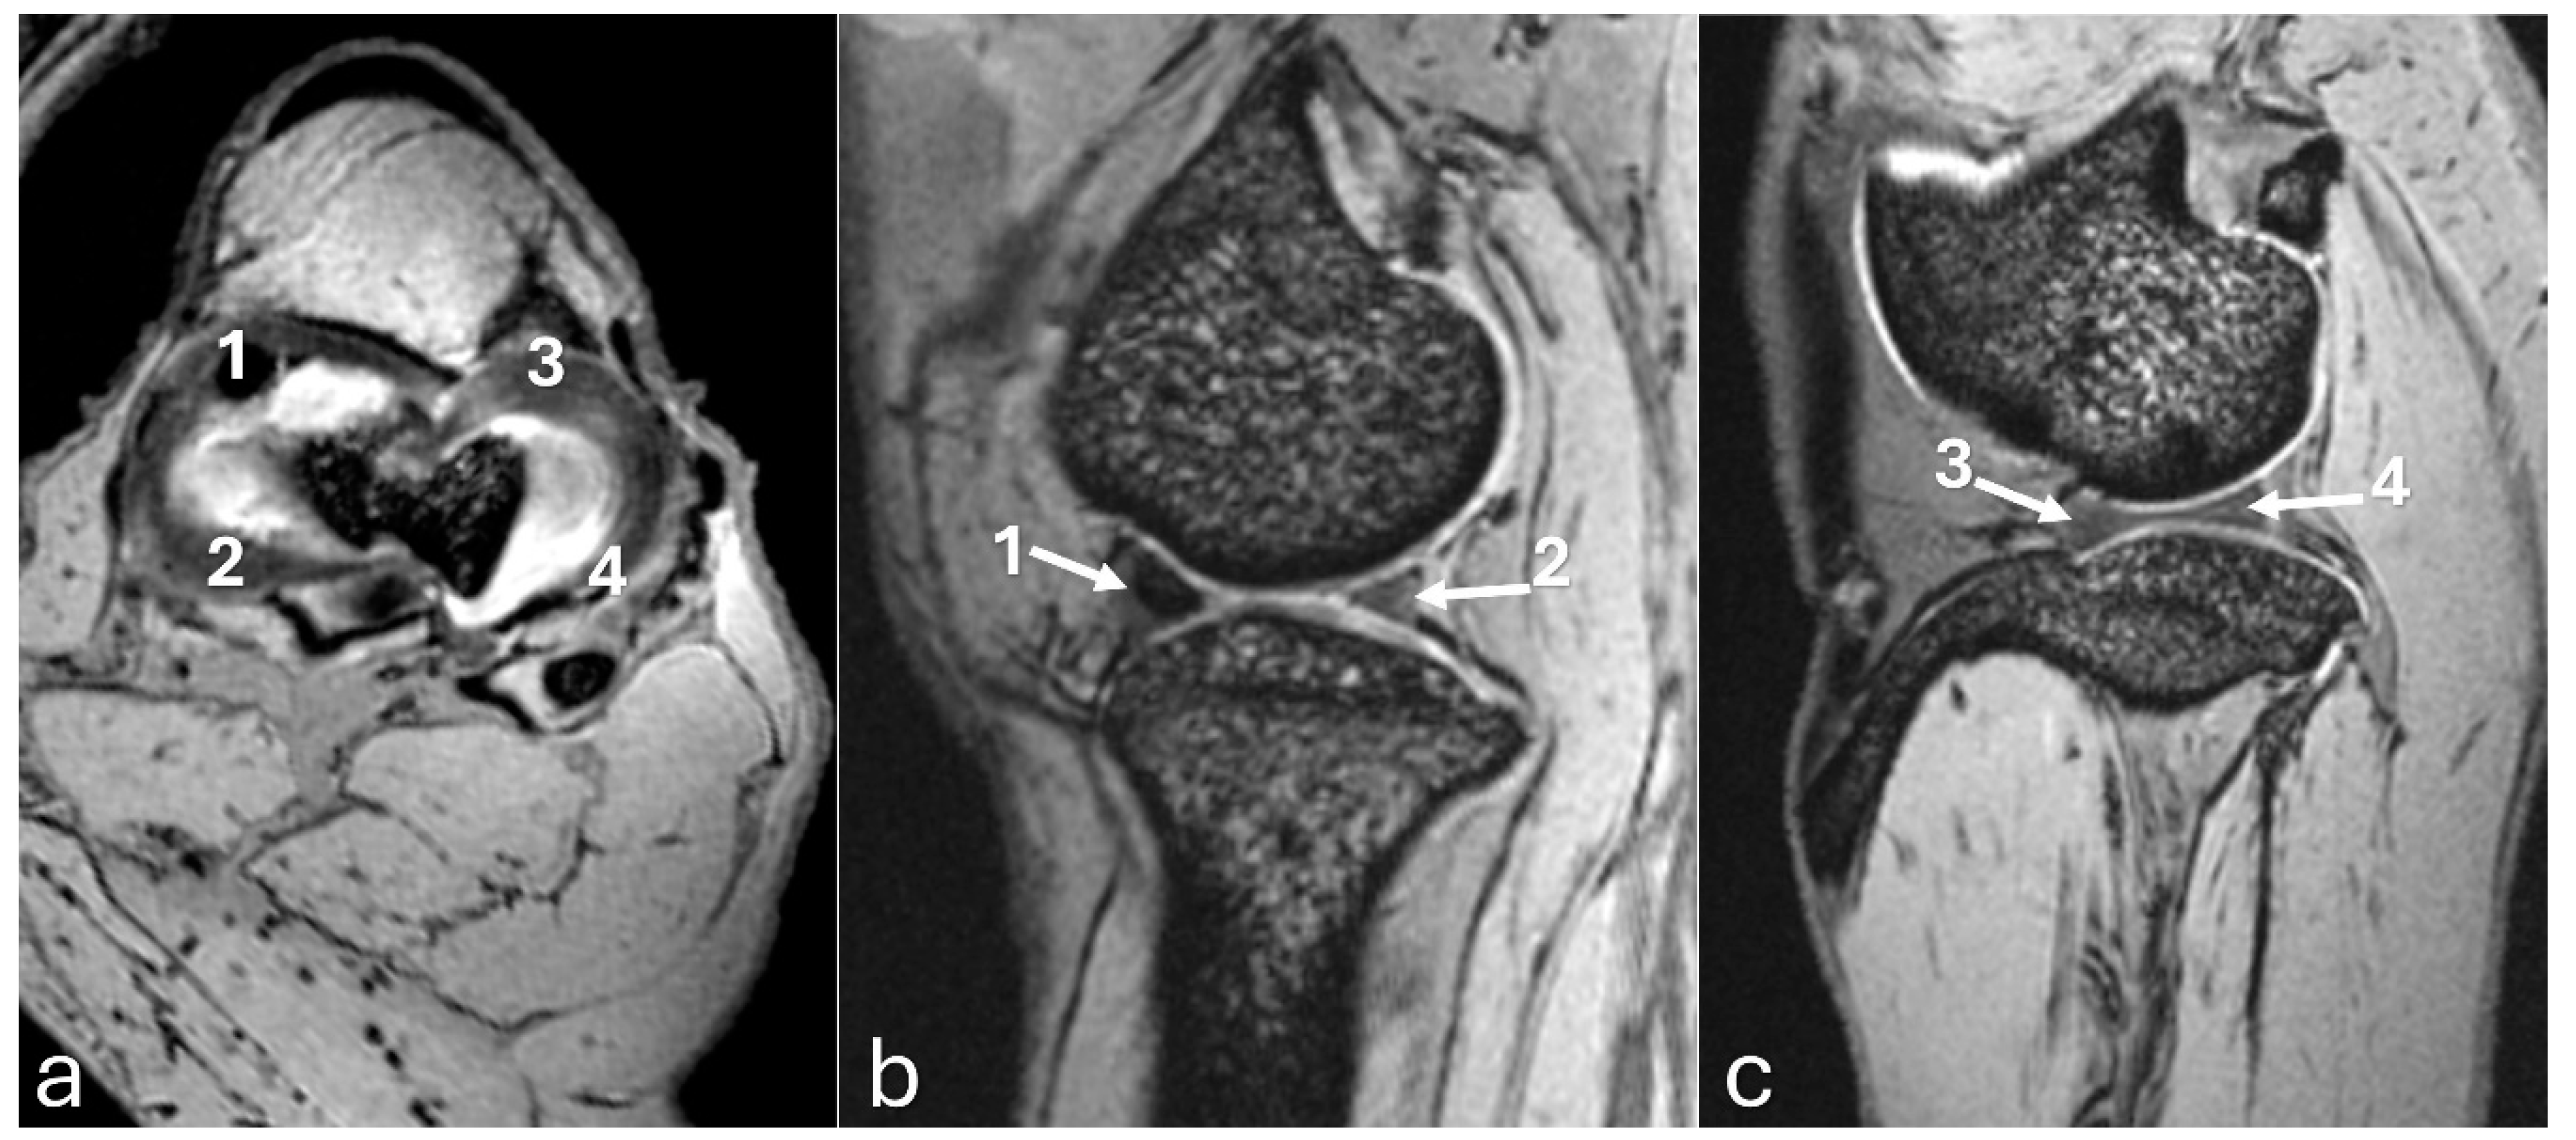

Figure 7. 3D-DESS imaging at 7-T MRI on transversal (a), sagittal (b), and dorsal (c) planes of an adult puma stifle joint (Puma concolor). Observe the medial meniscus (dashed arrow) and the mineralization of the cranial horn of the medial meniscus (arrow).

Figure 8. 3D-DESS imaging at 7-T MRI on transversal (a), and sagittal (b, c) planes of an adult puma stifle joint (Puma concolor). 1. Cranial horn of the medial meniscus. 2. Caudal horn of the medial meniscus. 3. Cranial horn of the lateral meniscus. 4. Caudal horn of the lateral meniscus. (a) Observe the C-type shape of both menisci on the transversal plane. (b, c) Note the triangle appearance of both menisci on the sagittal plane.

The MRI images allowed for more precise visualization of the cranial and caudal cruciate ligaments (Figure 6), the C-type shape of both menisci on the transverse plane, and the triangular appearance on the sagittal plane, with the medial meniscus being larger than the lateral one (Figure 7 and Figure 8). Mineralization was easily identified in the cranial horn of the medial meniscus as a rounded structure with a hypointense signal (3D-DESS sequence). High-resolution imaging of subchondral bone and cartilage was also visualized (Figure 9).